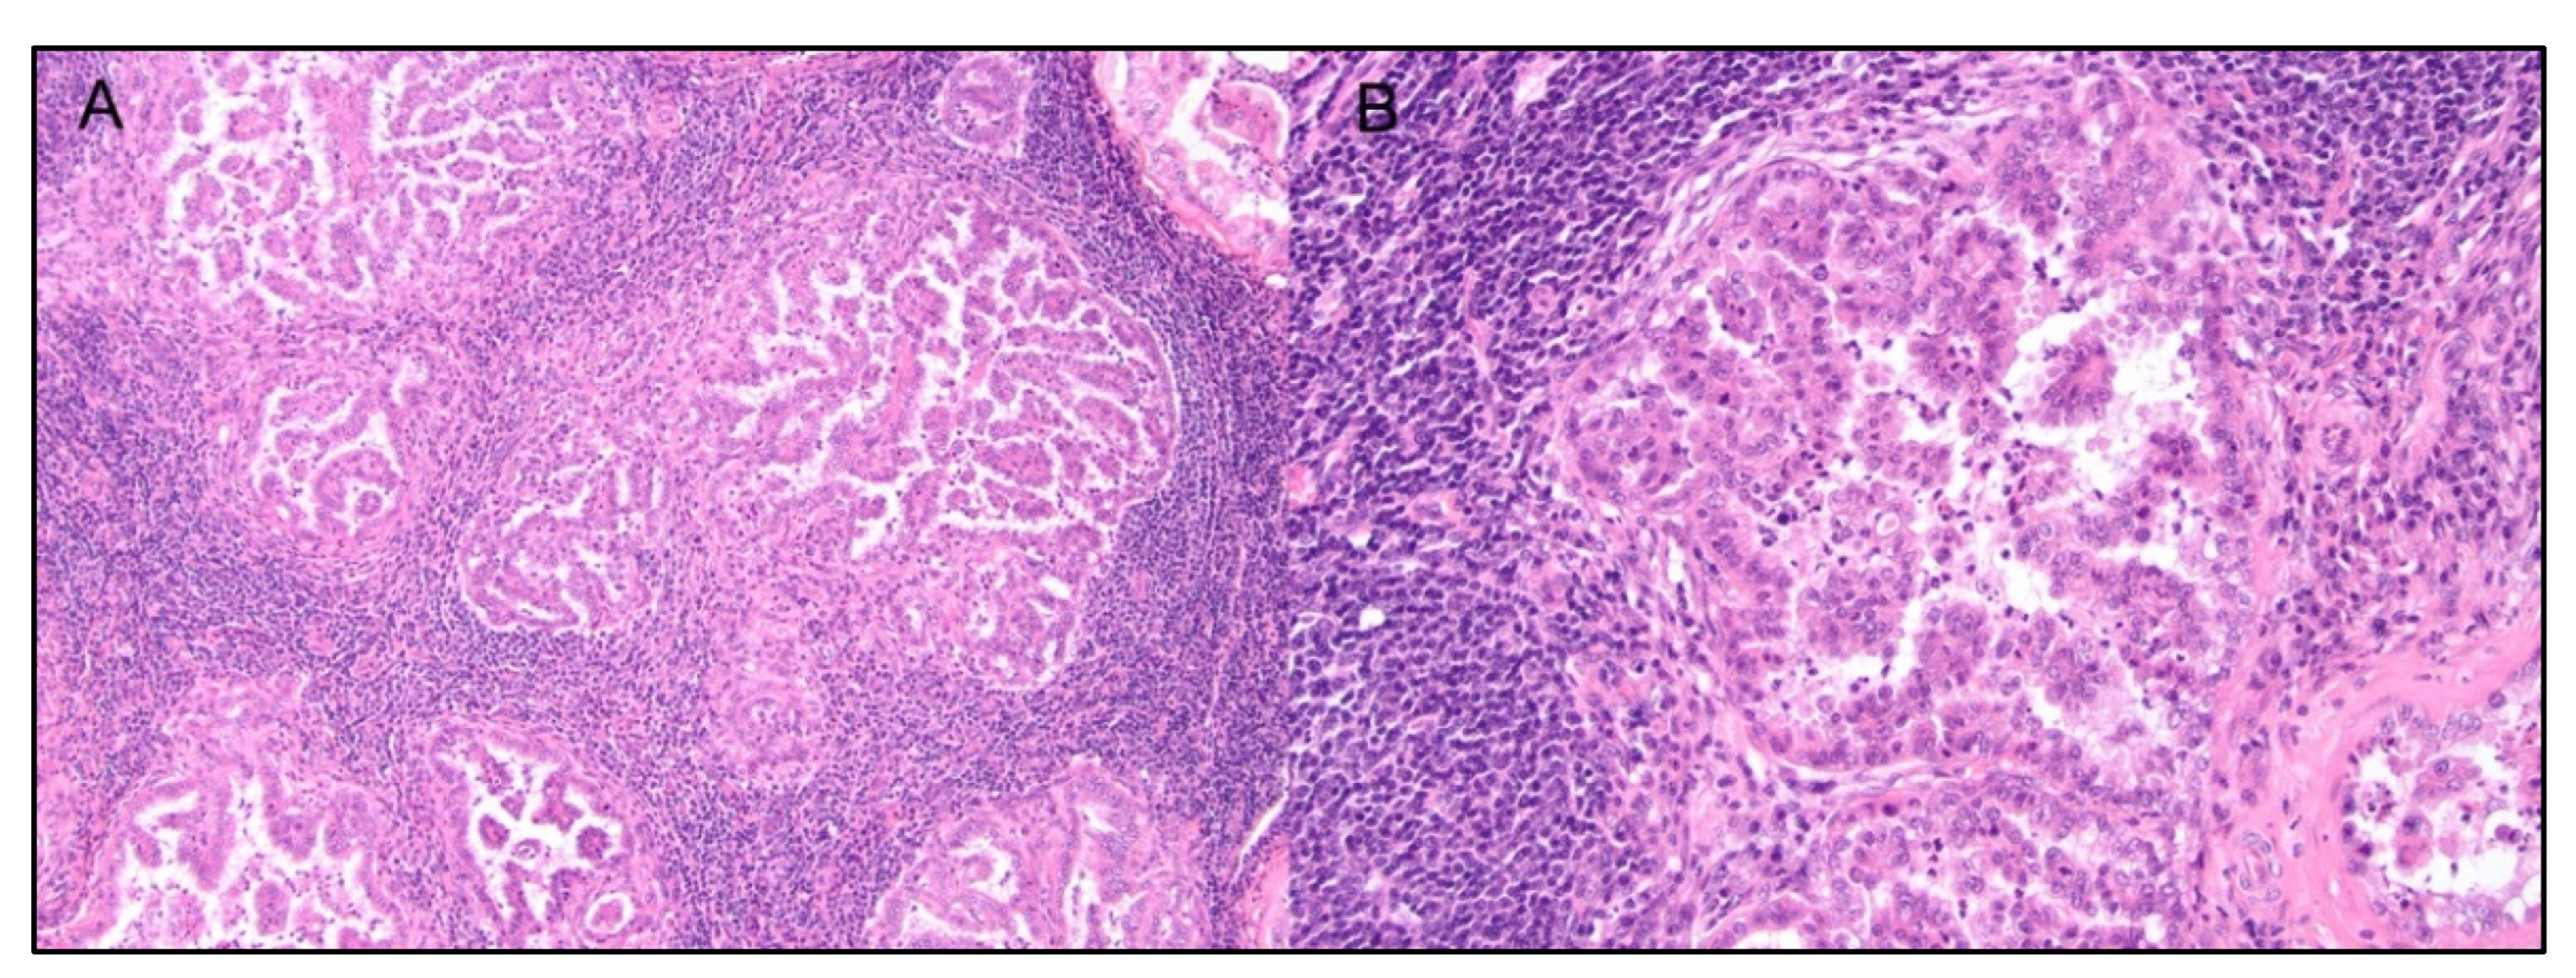

- Muscatello, L.V.; Avallone, G.; Brunetti, B.; Bacci, B.; Foschini, M.P.; Sarli, G. Standardized Approach for Evaluating Tumor Infiltrating Lymphocytes in Canine Mammary Carcinoma: Spatial Distribution and Score as Relevant Features of Tumor Malignancy. Vet. J. 2022, 283–284, 105833. [Google Scholar] [CrossRef] [PubMed]

- Lenz, J.A.; Assenmacher, C.-A.; Costa, V.; Louka, K.; Rau, S.; Keuler, N.S.; Zhang, P.J.; Maki, R.G.; Durham, A.C.; Radaelli, E.; et al. Increased Tumor-Infiltrating Lymphocyte Density Is Associated with Favorable Outcomes in a Comparative Study of Canine Histiocytic Sarcoma. Cancer Immunol. Immunother. 2021, 71, 807–818. [Google Scholar] [CrossRef] [PubMed]